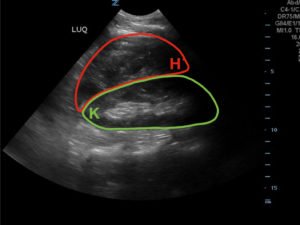

FAST Exam to Diagnose Subcapsular Renal Hematoma

A 49-year-old male presents for evaluation of hematuria and left flank pain after mechanical fall down stairs four days ago. Point-of-care ultrasound (POCUS) focused assessment with sonography in trauma (FAST) exam demonstrated subcapsular renal hematoma. Once a subcapsular hematoma is recognized the provider should keep in mind that this condition may be managed conservatively in patients with two normally functioning kidneys, but may require urgent intervention if the patient is at risk for significant renal disease, such as a single kidney. The use of bedside ultrasound can expedite diagnosis and care for these patients, and allow proper consultants to be contacted early. Some consultants that may need to be consulted include nephrology, urology, and/or internal medicine. This case report emphasizes the utility of the FAST exam for patients presenting for non-acute trauma. The FAST exam can be utilized not only to identify free fluid in the abdomen and pelvis but also to visualize organs and the surrounding tissues for abnormalities after a trauma.